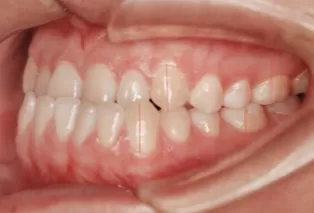

Intraoral photos